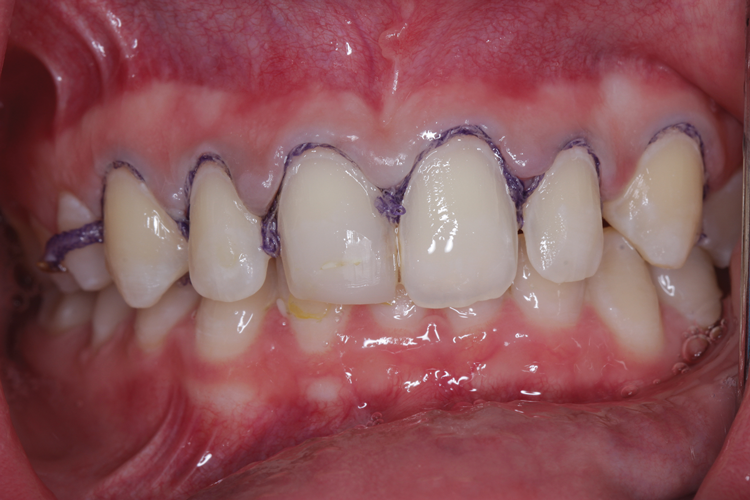

(2.) Minimal tooth preparation was completed to obtain a margin for the veneers while conserving as much enamel as possible. Gingival retraction cord was packed, and a final impression was made with a vinyl polysiloxane impression material.

Figure 2